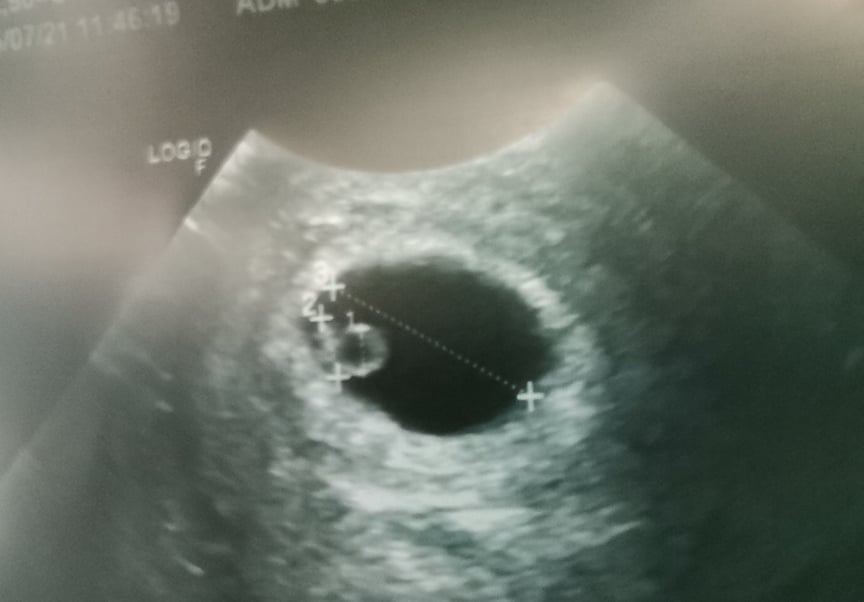

Jestem 6t0d i dzisiaj zobaczylam serduszko a malutek ma już 5mm :)

Załączniki

• 209965348_185109490295370_7472906094028850228_n.jpg

209965348_185109490295370_7472906094028850228_n.jpg

32,8 KB · Wyświetleń: 77